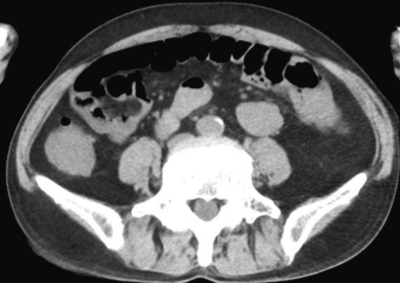

検査所見:血液所見:赤血球 299 万、Hb 9.7 g/dL、Ht 32 %、白血球 12,000、血小板 21 万。血液生化学所見:総蛋白 6.5 g/dL、アルブミン 3.6 g/dL、総ビリルビン 0.9 mg/dL、AST 28 U/L、ALT 22 U/L、LD 277 U/L (基準 176〜353)、γ-GTP 41 U/L (基準 8〜50)、アミラーゼ 80 U/L (基準 37〜160)、尿素窒素 18 mg/dL、クレアチニン 1.1 mg/dL、尿酸 6.7 mg/dL、血糖 128 mg/dL、Na 140 mEq/L、K 4.5 mEq/L、Cl 100 mEq/L。CRP 1.9 mg/dL。腹部単純 CT及び腹部造影 CTを別に示す。

腹部造影CT(動脈相)